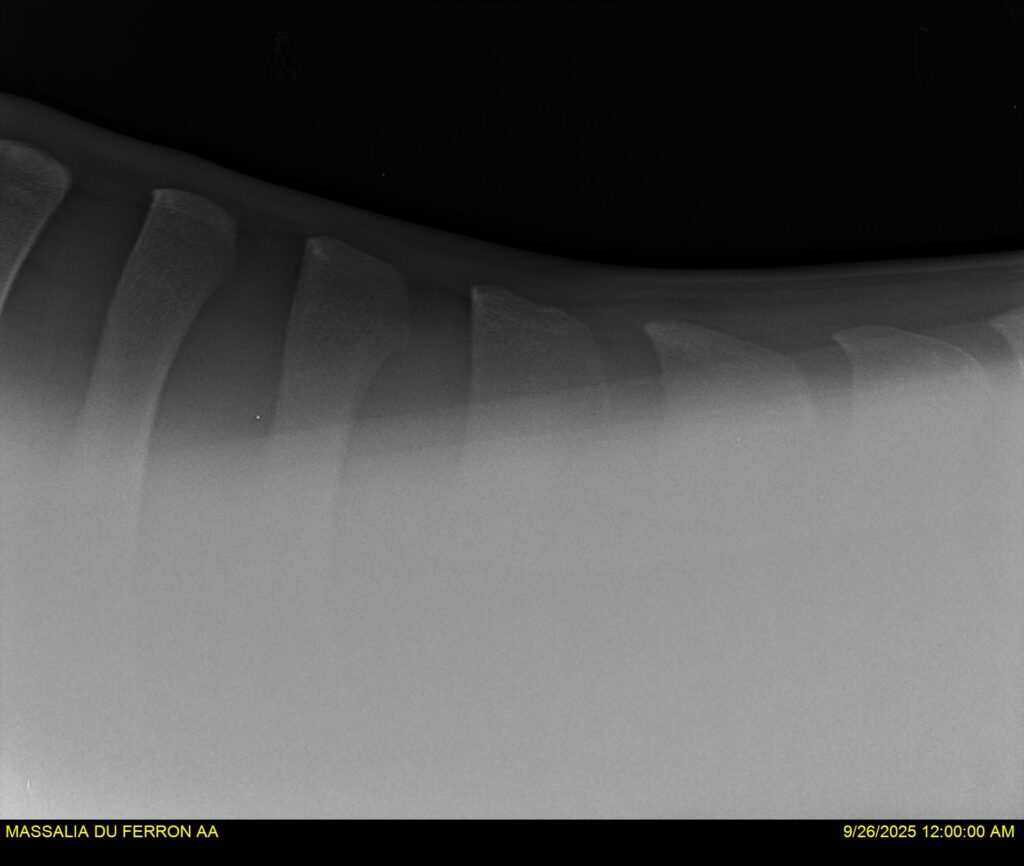

MASSALIA DU FERRON, jument qui prendra 4 ans par PRESTIGE KALONE x TRESOR DU RENOM. Un mental en or et un véritable sens de la barre ! Facile d’accès ! Bonne énergie et bons moyens. Souche moderne et très intéressante. Transport OK, maréchalerie OK, santé RAS, Bilan clichés radios OK.

RADIOS et COMPTE RENDU